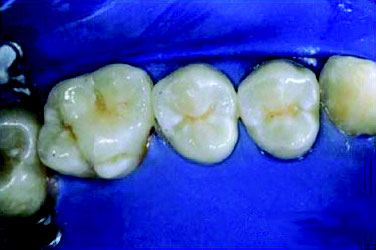

Pit and Fissure Caries (Figure 2). Includes Class I occlusal surfaces of posterior teeth, lingual pits of maxillary incisors, buccal surfaces of mandibular molars.

Figure 2. Pit and fissure caries.

Figure 2